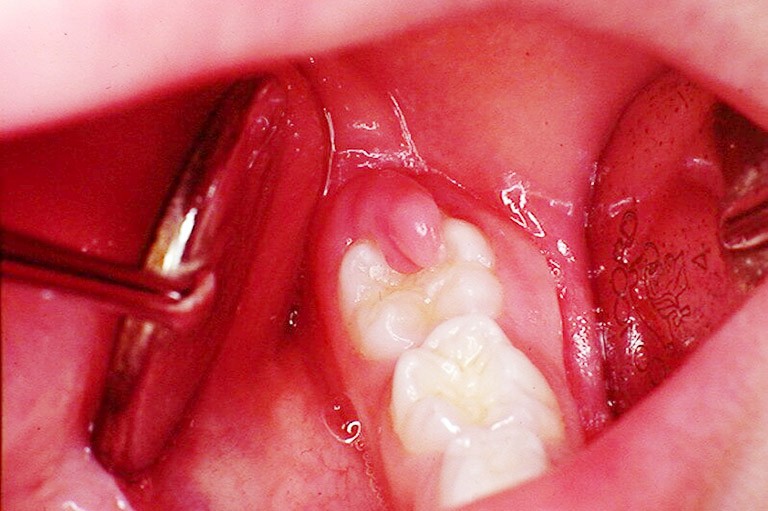

Sưng lợi mọc răng khôn là tình trạng viêm của mô bao quanh răng khôn. Nguyên nhân chính là do răng khôn mọc lệch, mọc ngầm làm tổn thương nướu răng. Khi đó, vi khuẩn sẽ có cơ hội xâm nhập khu vực xung quanh nướu, gây nhiễm trùng,

sưng đau răng lợi.

Sưng lợi răng khôn là tình trạng viêm của mô bao quanh răng khôn